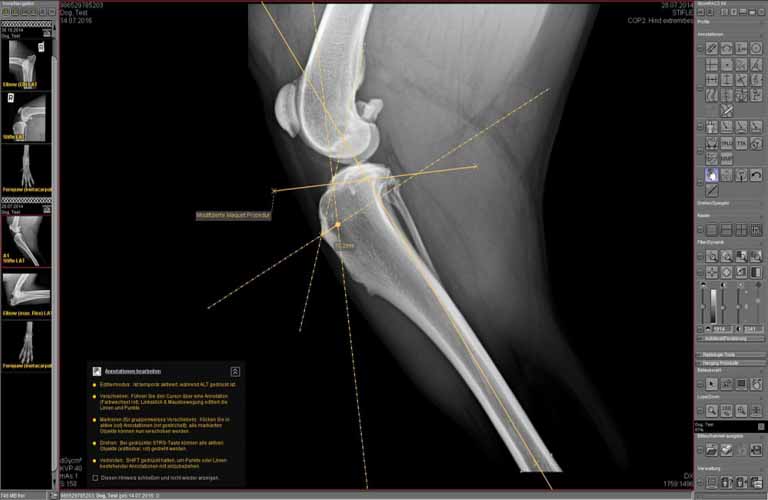

Röntgenbilder in digitaler Form bieten spezielle Möglichkeiten der Bildbetrachtung. So können beispielsweise Weichteile und Knochen mit einem Spezialfilter in ein und derselben Aufnahme sichtbar gemacht werden. Zahlreiche Annotationen erleichtern die Vermessung bei häufig auftretenden Diagnosen, zum Beispiel die Vermessungshilfen für TPLO, TTA, HD, Distraktionsindex, Herzvermessung nach Buchanan etc.

Mit den Tools der Bildbearbeitung (beispielsweise Pfeile, Kreise oder Winkel) können die Aufnahmen auch Tierbesitzern anschaulich erklärt werden. Diese haben dadurch die Möglichkeit, die Diagnose und die entsprechende Behandlung nachzuvollziehen.